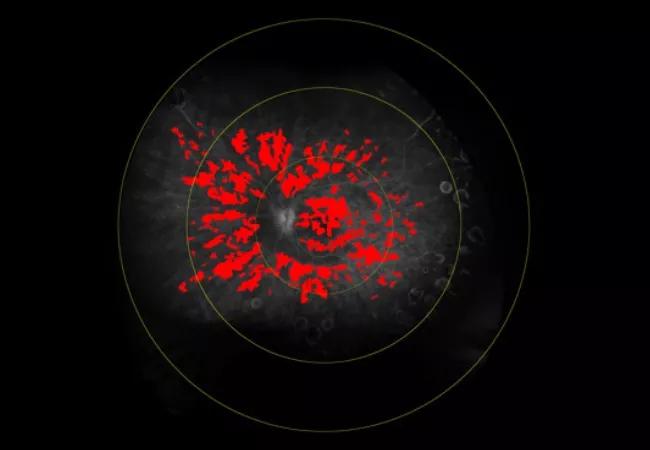

Retinal leakage on fluorescein angiography

Imaging of patient with intraocular inflammation

Figure 1. A patient presents with active disease. AC cell density is 36.41 cells/mm3. Central subfield thickness (CST) is normal. Total retinal leakage (total leakage index, TLI) is 19.5%.